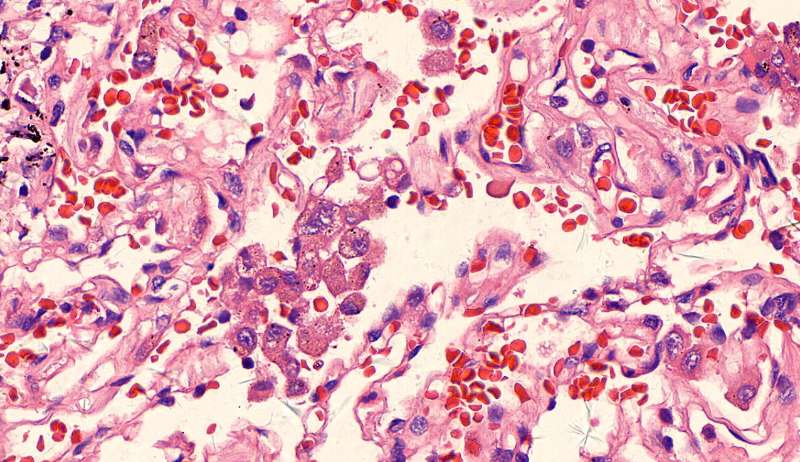

第三例

许多小白球--隐球菌,不做PAS及六铵银特染也看得清 荚膜的感觉明显 第三例的CT